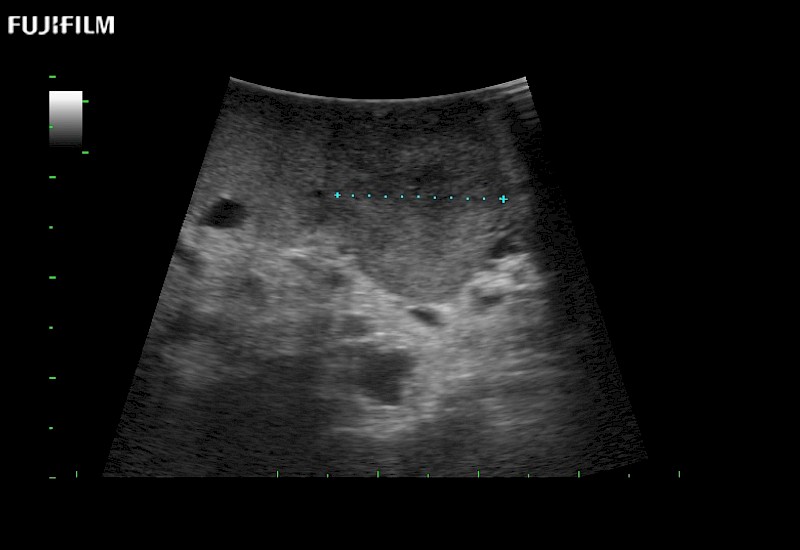

for use during open and laparoscopic procedures: Tumor localization & staging, Ablation, Resection, Biopsy, Transplant, Abdominal exploration, Robotic surgery

Our dedication to Surgical Oncology allows us to offer superior image quality, outstanding system reliability and intuitive use of cutting edge technology.